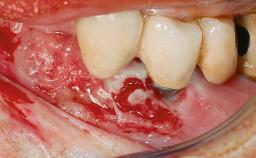

Peri-implantitis Treated with Access-Flap Surgery

A 27-year-old male was referred to the periodontist for assessment and management of implant site 41. The implant had been placed nine years previously and restored with a screw-retained single crown. The patient was a cigarette smoker in good general health. He reported he had reduced his smoking habit from 25 cigarettes per day to 15 cigarettes per day in the previous six months. On examination, there was calculus and plaque present at the lower anterior teeth and at implant site 41. Localized attachment loss was observed at teeth 32 and 42, with 2–3 mm of gingival recession. At implant site 41, there were 8–9 mm probing depths with suppuration and bleeding on probing.